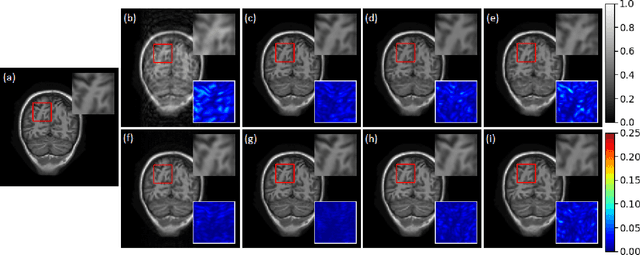

Compressive sensing magnetic resonance imaging (CS-MRI) accelerates the acquisition of MR images by breaking the Nyquist sampling limit. In this work, a novel generative adversarial network (GAN) based framework for CS-MRI reconstruction is proposed. Leveraging a combination of patchGAN discriminator and structural similarity index based loss, our model focuses on preserving high frequency content as well as fine textural details in the reconstructed image. Dense and residual connections have been incorporated in a U-net based generator architecture to allow easier transfer of information as well as variable network length. We show that our algorithm outperforms state-of-the-art methods in terms of quality of reconstruction and robustness to noise. Also, the reconstruction time, which is of the order of milliseconds, makes it highly suitable for real-time clinical use.